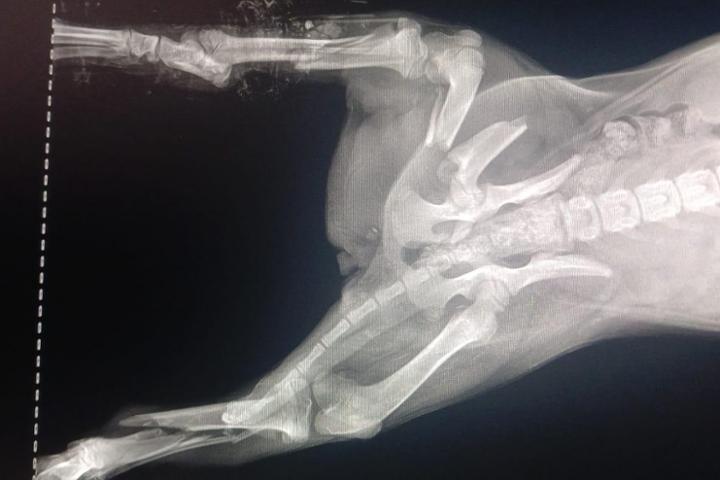

Le but de Hajar Aourz est de prendre soin des chats et chiens errants au Maroc à Salé. Nourrir les animaux des refuges et ceux des rues, vacciner et stériliser un maximun de chats et de chiens afin de diminuer la prolifération des maladies et des naissances. Cela évitera des souffrances inutiles, des vies misérables et la mort. Hajar recueille dans ses 2 refuges, des chats et des chiens malades ou accidentés. Ils sont soignés, opérés, nourris et proposés à l'adoption pour enfin une vie digne. Des parrains et marraines sont bienvenus (chat 30 € - chien 40€). Les adoptions sont inexistantes au Maroc. Il faut donc préparer les candidats à l'adoption pour d'autres pays comme la France, la Suisse, etc... Les coûts (vaccin rage, sérologie, identification, passeport, vol en avion) sont importants. Ils ont besoin d'aide et nous vous remercions infiniment de votre soutien. Paypal: zizou608@yahoo.fr ou carolrossier@hotmail.com RIB: FR76 1751 5900 0004 9650 2199 085 BIC: CEPAFRPP751